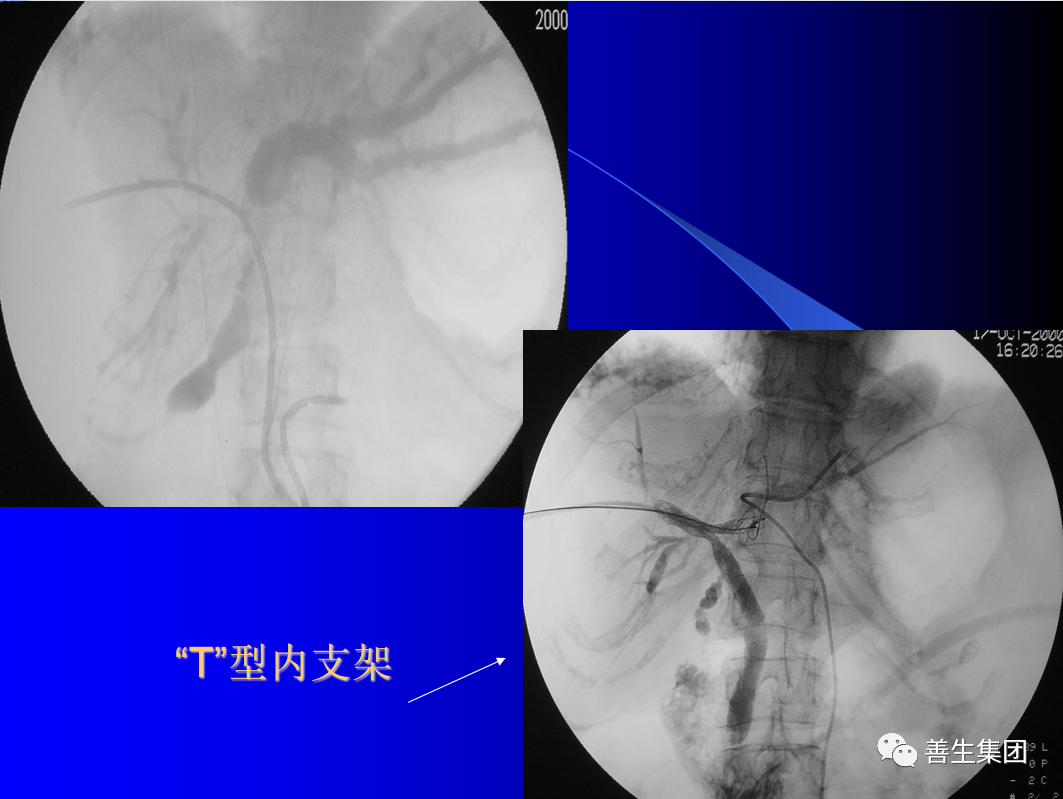

胆管支架植入后阻塞的原因包括支架内肿瘤生长、支架两端肿瘤过度生长及胆汁淤泥形成等。经皮穿肝胃小弯途径可避开肿瘤和狭窄段,适用于肝门以下胆管完全梗阻,不能建立引流通道的病例。